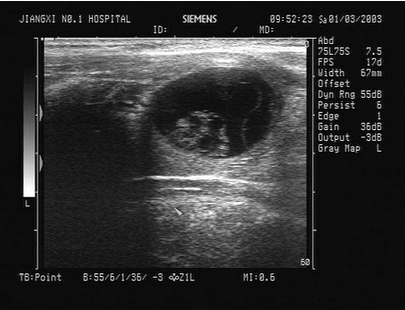

3、单项选择题

男,18岁,外伤1小时就诊。结合超声声像图,诊断为()

A.脾外伤血肿

B.脾淋巴管瘤

C.膈下积液

D.脾皮样囊肿

E.脾血管瘤